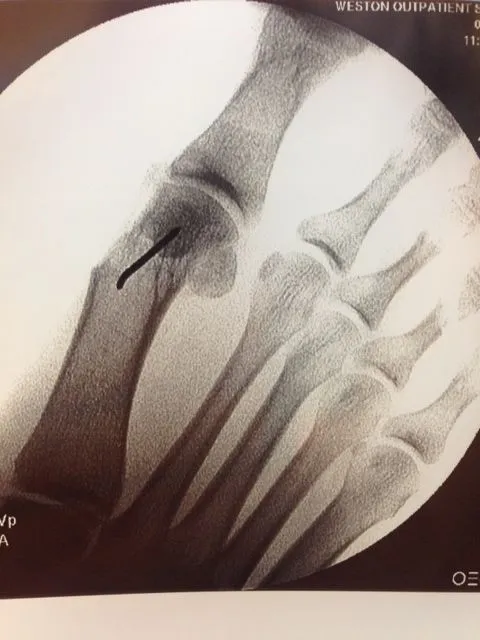

During surgical correction of the bunion a v-shape bone is made in most cases to translate the head of the 1st metatarsal laterally which creates an overhang of bone from the previous position of the bone (pictured left). The overhang is remove and the new position of the bone is held with some type of fixation which varies from screws, staples, or pins which is the case here. The pin is buried left in permanently (pictured right).